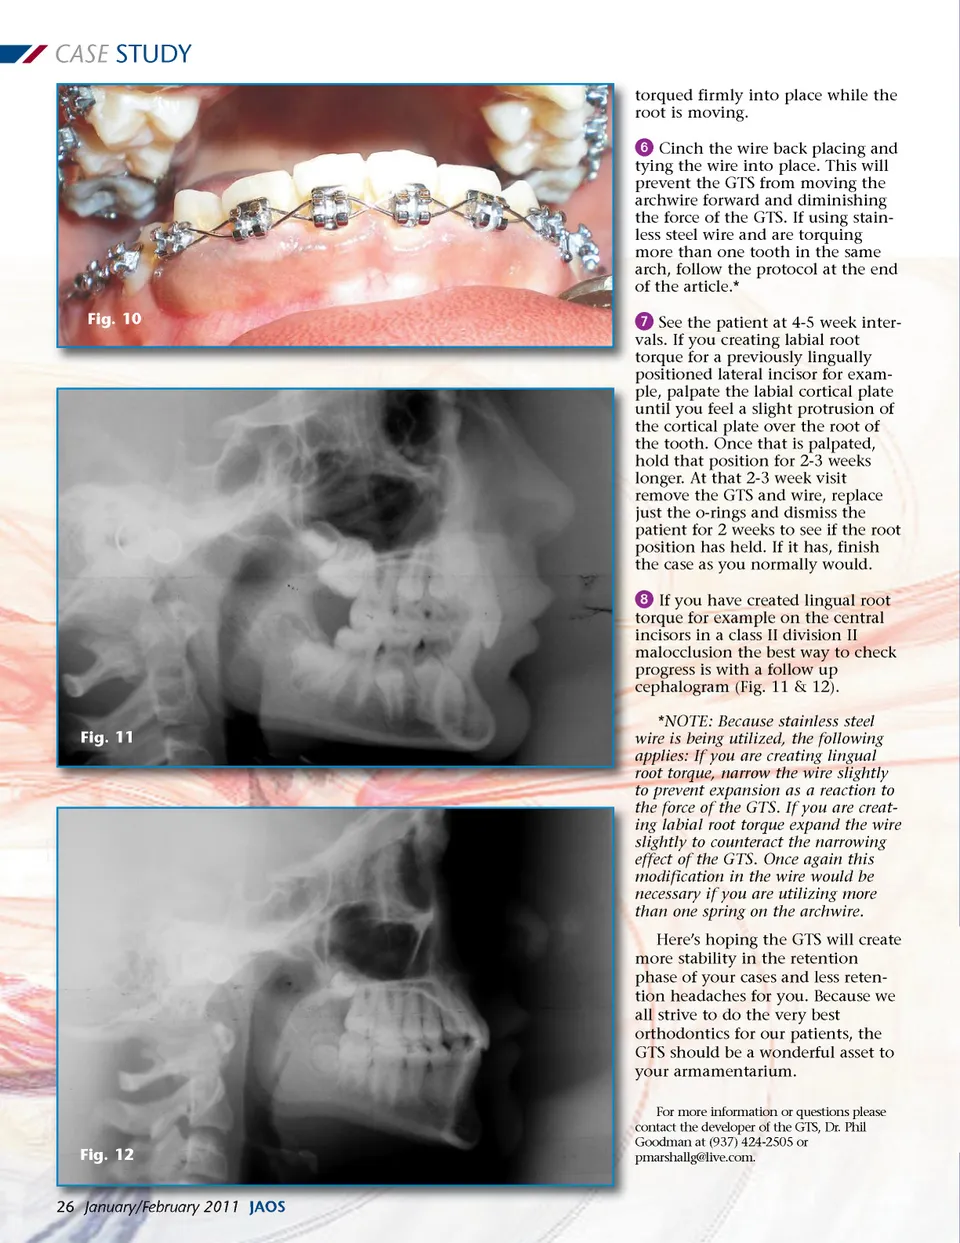

CASE STUDY torqued firmly into place while the root is moving. ᕦ Cinch the wire back placing and tying the wire into place. This will prevent the GTS from moving the archwire forward and diminishing the force of the GTS. If using stain-less steel wire and are torquing more than one tooth in the same arch, follow the protocol at the end of the article.* Fig. 10 ᕧ See the patient at 4-5 week inter-vals. If you creating labial root torque for a previously lingually positioned lateral incisor for exam-ple, palpate the labial cortical plate until you feel a slight protrusion of the cortical plate over the root of the tooth. Once that is palpated, hold that position for 2-3 weeks longer. At that 2-3 week visit remove the GTS and wire, replace just the o-rings and dismiss the patient for 2 weeks to see if the root position has held. If it has, finish the case as you normally would. ᕨ If you have created lingual root torque for example on the central incisors in a class II division II malocclusion the best way to check progress is with a follow up cephalogram (Fig. 11 & 12). Fig. 11 *NOTE: Because stainless steel wire is being utilized, the following applies: If you are creating lingual root torque, narrow the wire slightly to prevent expansion as a reaction to the force of the GTS. If you are creat-ing labial root torque expand the wire slightly to counteract the narrowing effect of the GTS. Once again this modification in the wire would be necessary if you are utilizing more than one spring on the archwire. Here’s hoping the GTS will create more stability in the retention phase of your cases and less reten-tion headaches for you. Because we all strive to do the very best orthodontics for our patients, the GTS should be a wonderful asset to your armamentarium. For more information or questions please contact the developer of the GTS, Dr. Phil Goodman at (937) 424-2505 or pmarshallg@live.com. Fig. 12 26 January/February 2011 JAOS